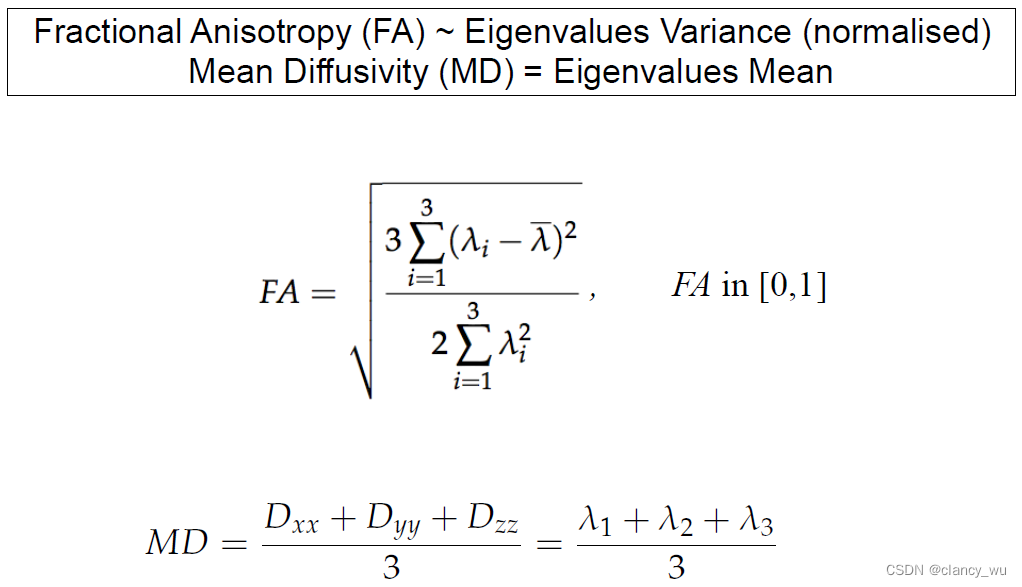

由此,可以得出各向异性的表达公式。各向异性的全称其实是Fractional Anisotropy,FA值,在[0, 1]之间。MD是平均扩散率

如下图: